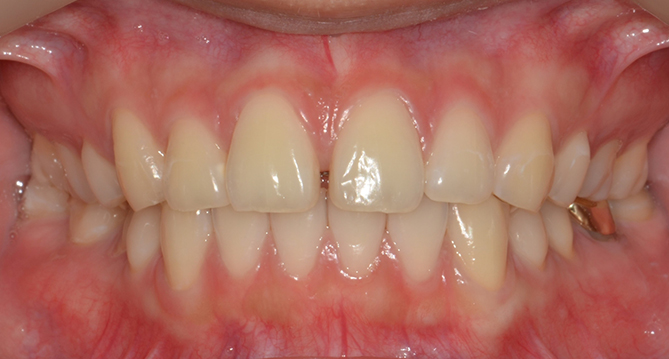

교합과 심미성을 모두 만족시키는

완벽을 추구하는 교정치료를 진행합니다.

풍부한 경험을 보유한 의료진이 직접 상담부터 유지, 치료까지 책임지고

개개인의 구강상태에 따른 적합한 최선의 치료계획을 수립하고 치료합니다.

개인의 얼굴형태나 아래위턱뼈의 형태, 성장발달 단계 등 여러가지를 고려해

치료계획을 세우는 교정은 정밀진단을 통한 올바른 치료가 중요합니다.

클리피씨교정장치

클리피씨교정장치는 치아색과 유사하며,

균등한 힘을 유지해 통증이 적습니다.

초기 교정기간을 단축시켜준다는 장점이 있습니다.

연세새빛치과 전체치아교정[클리피씨] 교정 전

연세새빛치과 전체치아교정[클리피씨] 교정 후